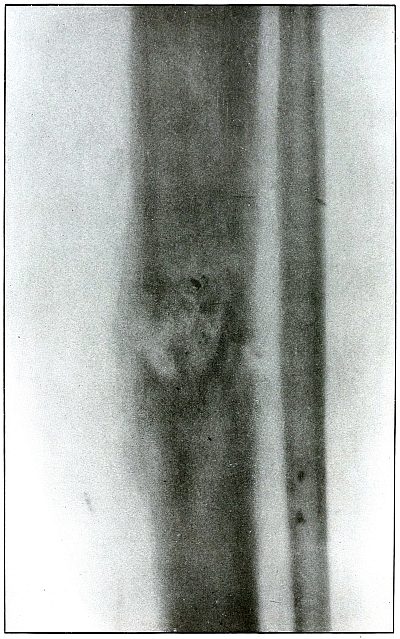

[Pg 122]

Plate 56.

[Pg 123]

Rifle—Plate 56.

LOWER EXTREMITY.

Gunshot Fracture Below the Middle of the Femur,

with Lodgment of the Bullet Near the Fracture.

The course of the projectile was transverse. The long splitting

fracture, with few large fragments and the lodged undeformed missile,

indicate that the injury to the bone was caused by the missile

striking the bone with large cross section or at an inclined angle so

that all of the remaining energy of the projectile at long range was

absorbed by the bone.

Had the point of the ball struck the bone with the same energy, it

would have produced smaller fragments and might then have passed

beyond the bone. The normal size of the diameter, slightly shortened

length, greater density of the point of the shadow, shows the bullet

to lie behind the bone with its nose pointing slightly backward. The

actual length of the bullet is 1.25 inches: the length of the shadow

is 1 inch.

Treatment and results would be about the same as in

plates 49 and 50.

[Pg 124]